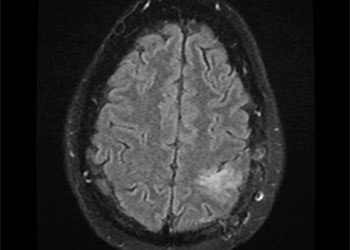

Cerebral Metastases from Non-Small Cell Lung Cancer

Author: Xavier P. J. Gaudin D.O., F.A.C.O.S., Read More!